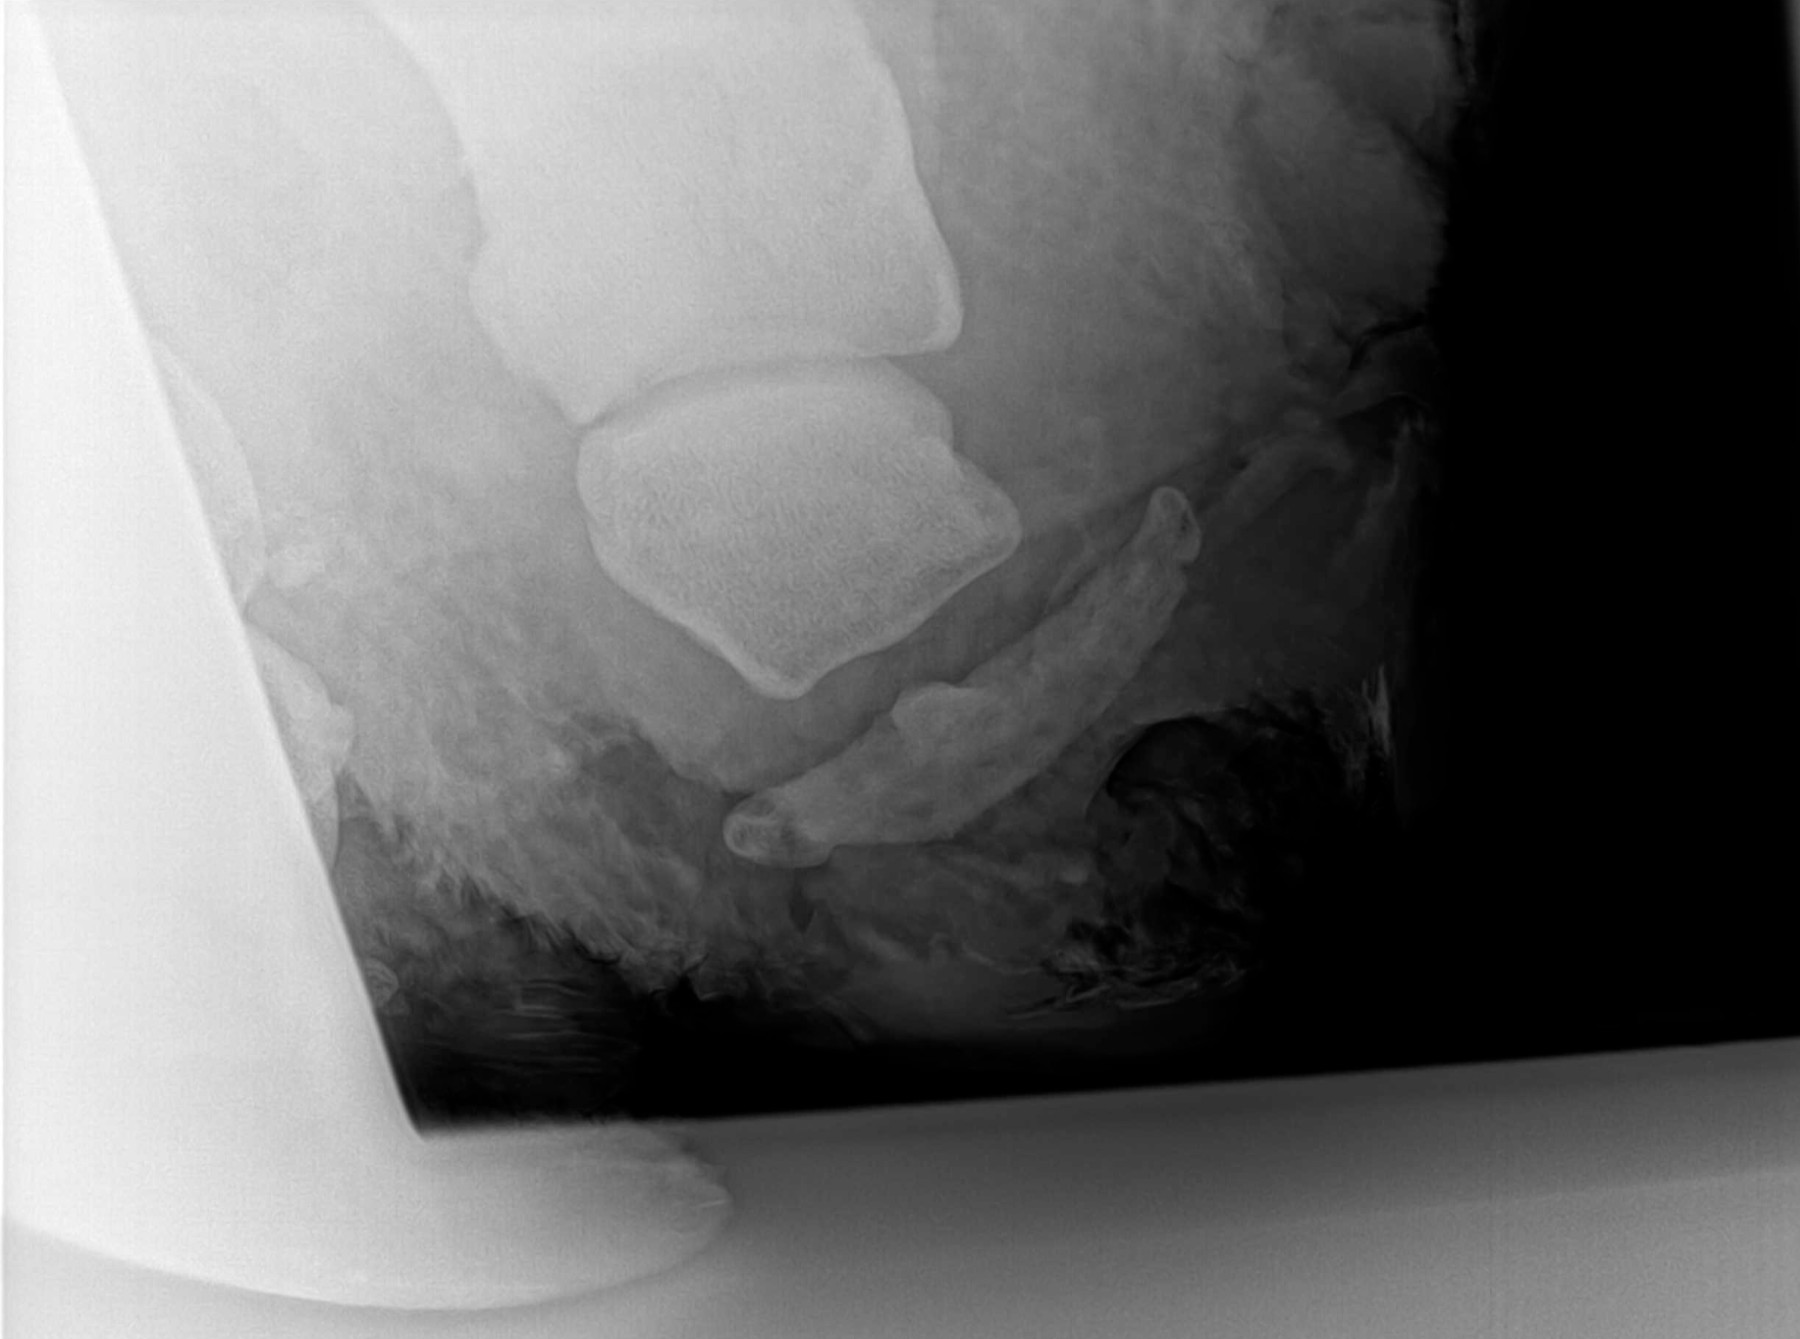

Radiología Digital como Herramienta Complementaria en el Dictamen de Bienes Muebles